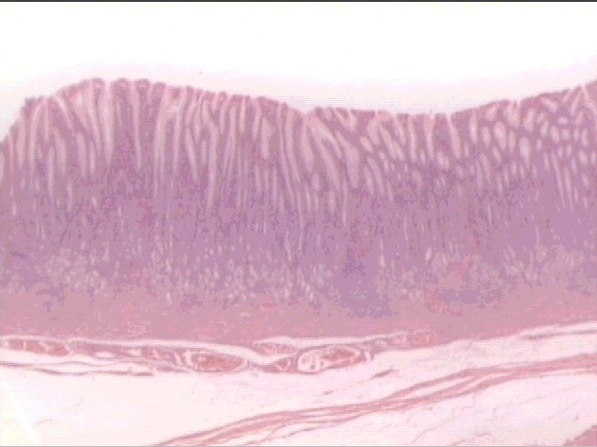

esophagus

esophageal glands

lumen

SSE nonkeratinized

muscularis mucosa

submucosa